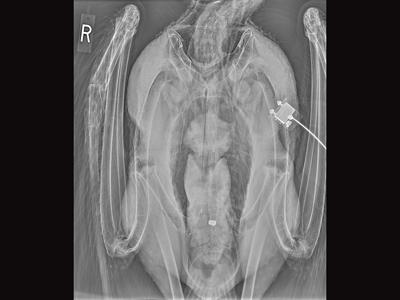

An X-ray photo depicts a lead .22 LR bullet ingested by a condor that died of lead toxicosis. Lead ammunition in carcasses left behind by hunters is the leading killer for condors.

There are a handful of animals in California synonymous with conservation efforts. Among them are condors, a beloved scavenger and one of the world’s rarest birds. Once brought to the brink of extinction partly due to lead poisoning from eating carcasses containing bullet fragments, condors are now protected through regulations requiring hunters and ranchers to use non-lead ammunition.